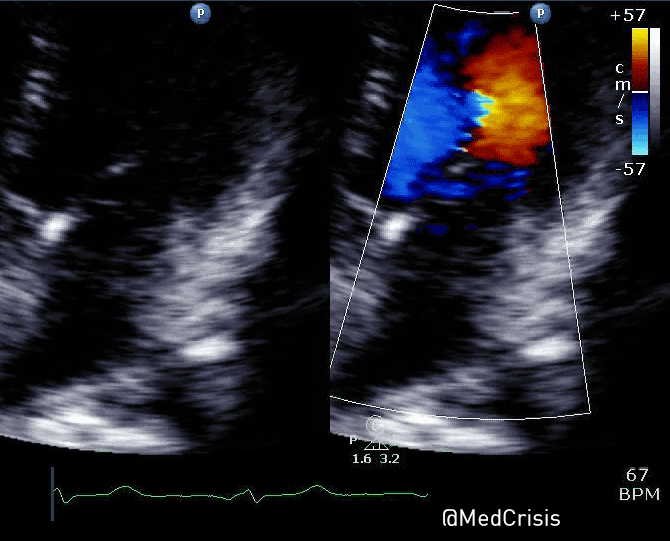

This parasternal short axis view gives the clearest demonstration of the problem. A regional wall motion abnormality is clearly seen affected the infero-septum and inferior wall. The rest of the left ventricle is contracting well.

The anterolateral papillary muscle is connected to the anterior mitral valve leaflet and receives a blood supply from both the left anterior descending artery (via a diagonal) and the circumflex artery (via an obtuse marginal). However the posteromedial papillary muscle only has one blood supply, which is the posterior descending artery, a branch of the right coronary artery in 90% of people.

Therefore one can appreciate why mitral valve problems are more common following an inferior STEMI. In this case an almost akinetic segment, which included the posteromedial papillary muscle, caused the posterior mitral valve leaflet to become fixed, causing mitral regurgitation. Even though overall left ventricular function was only mildly impaired on the echocardiogram, the regurgitant pressure into the lungs can precipitate pulmonary oedema.